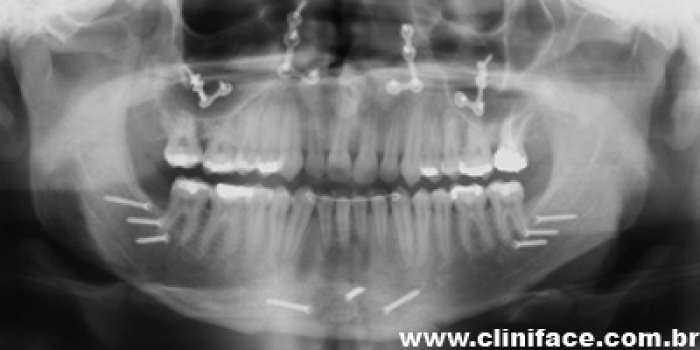

Rx final